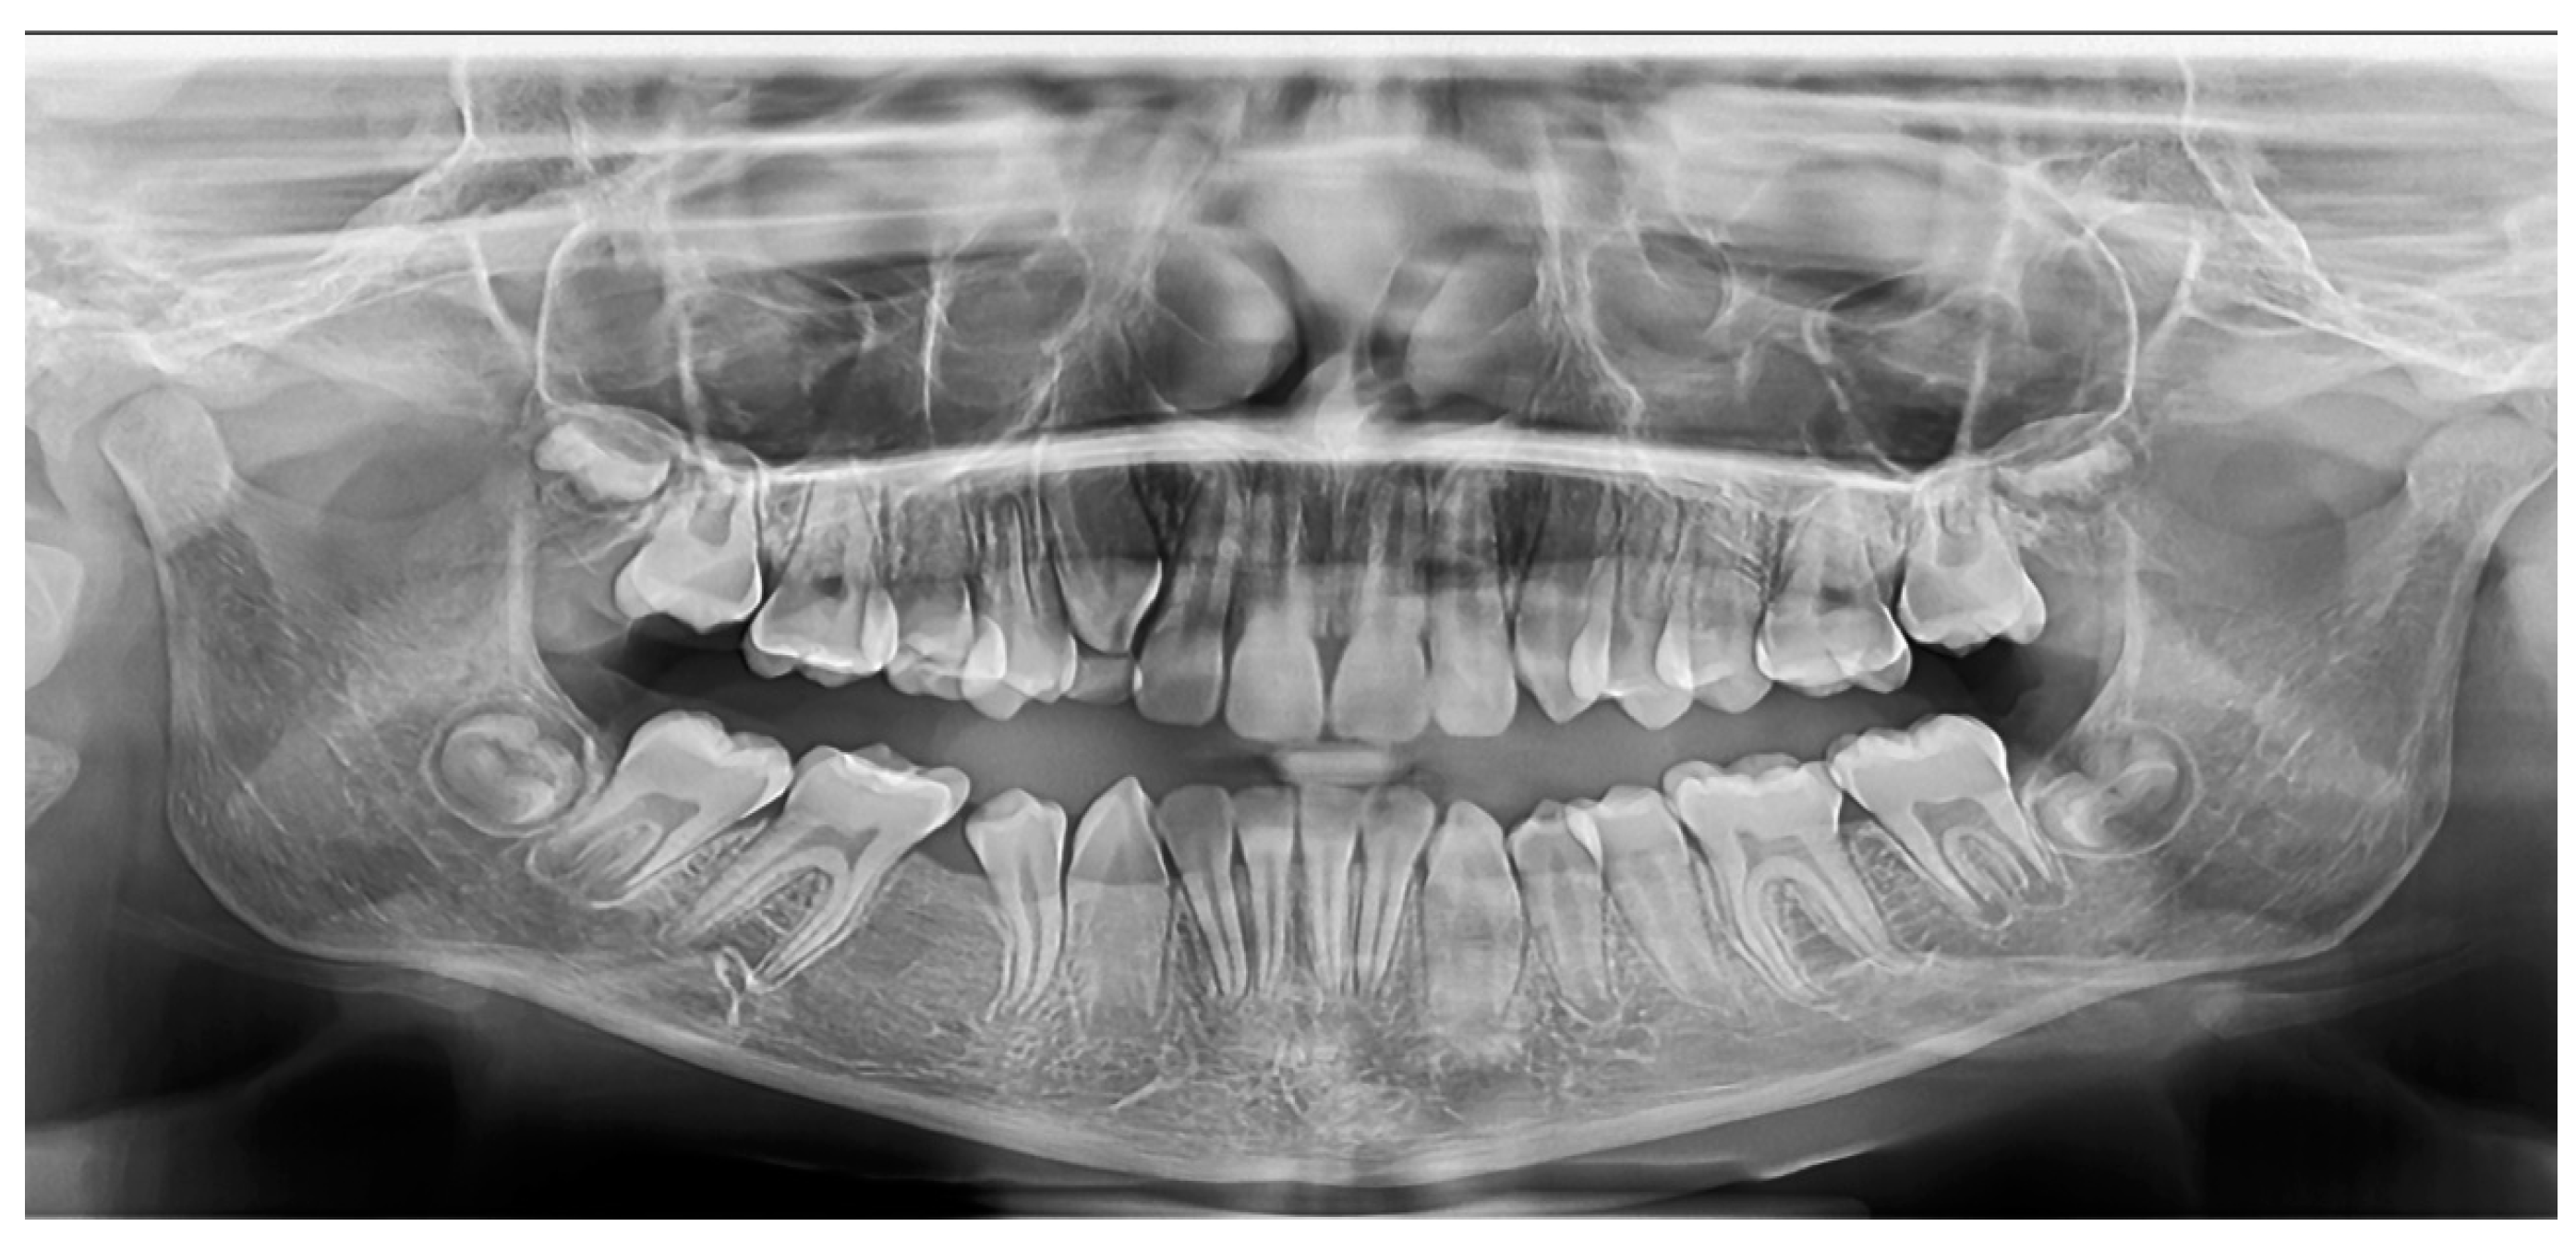

2.2.3. Case 3